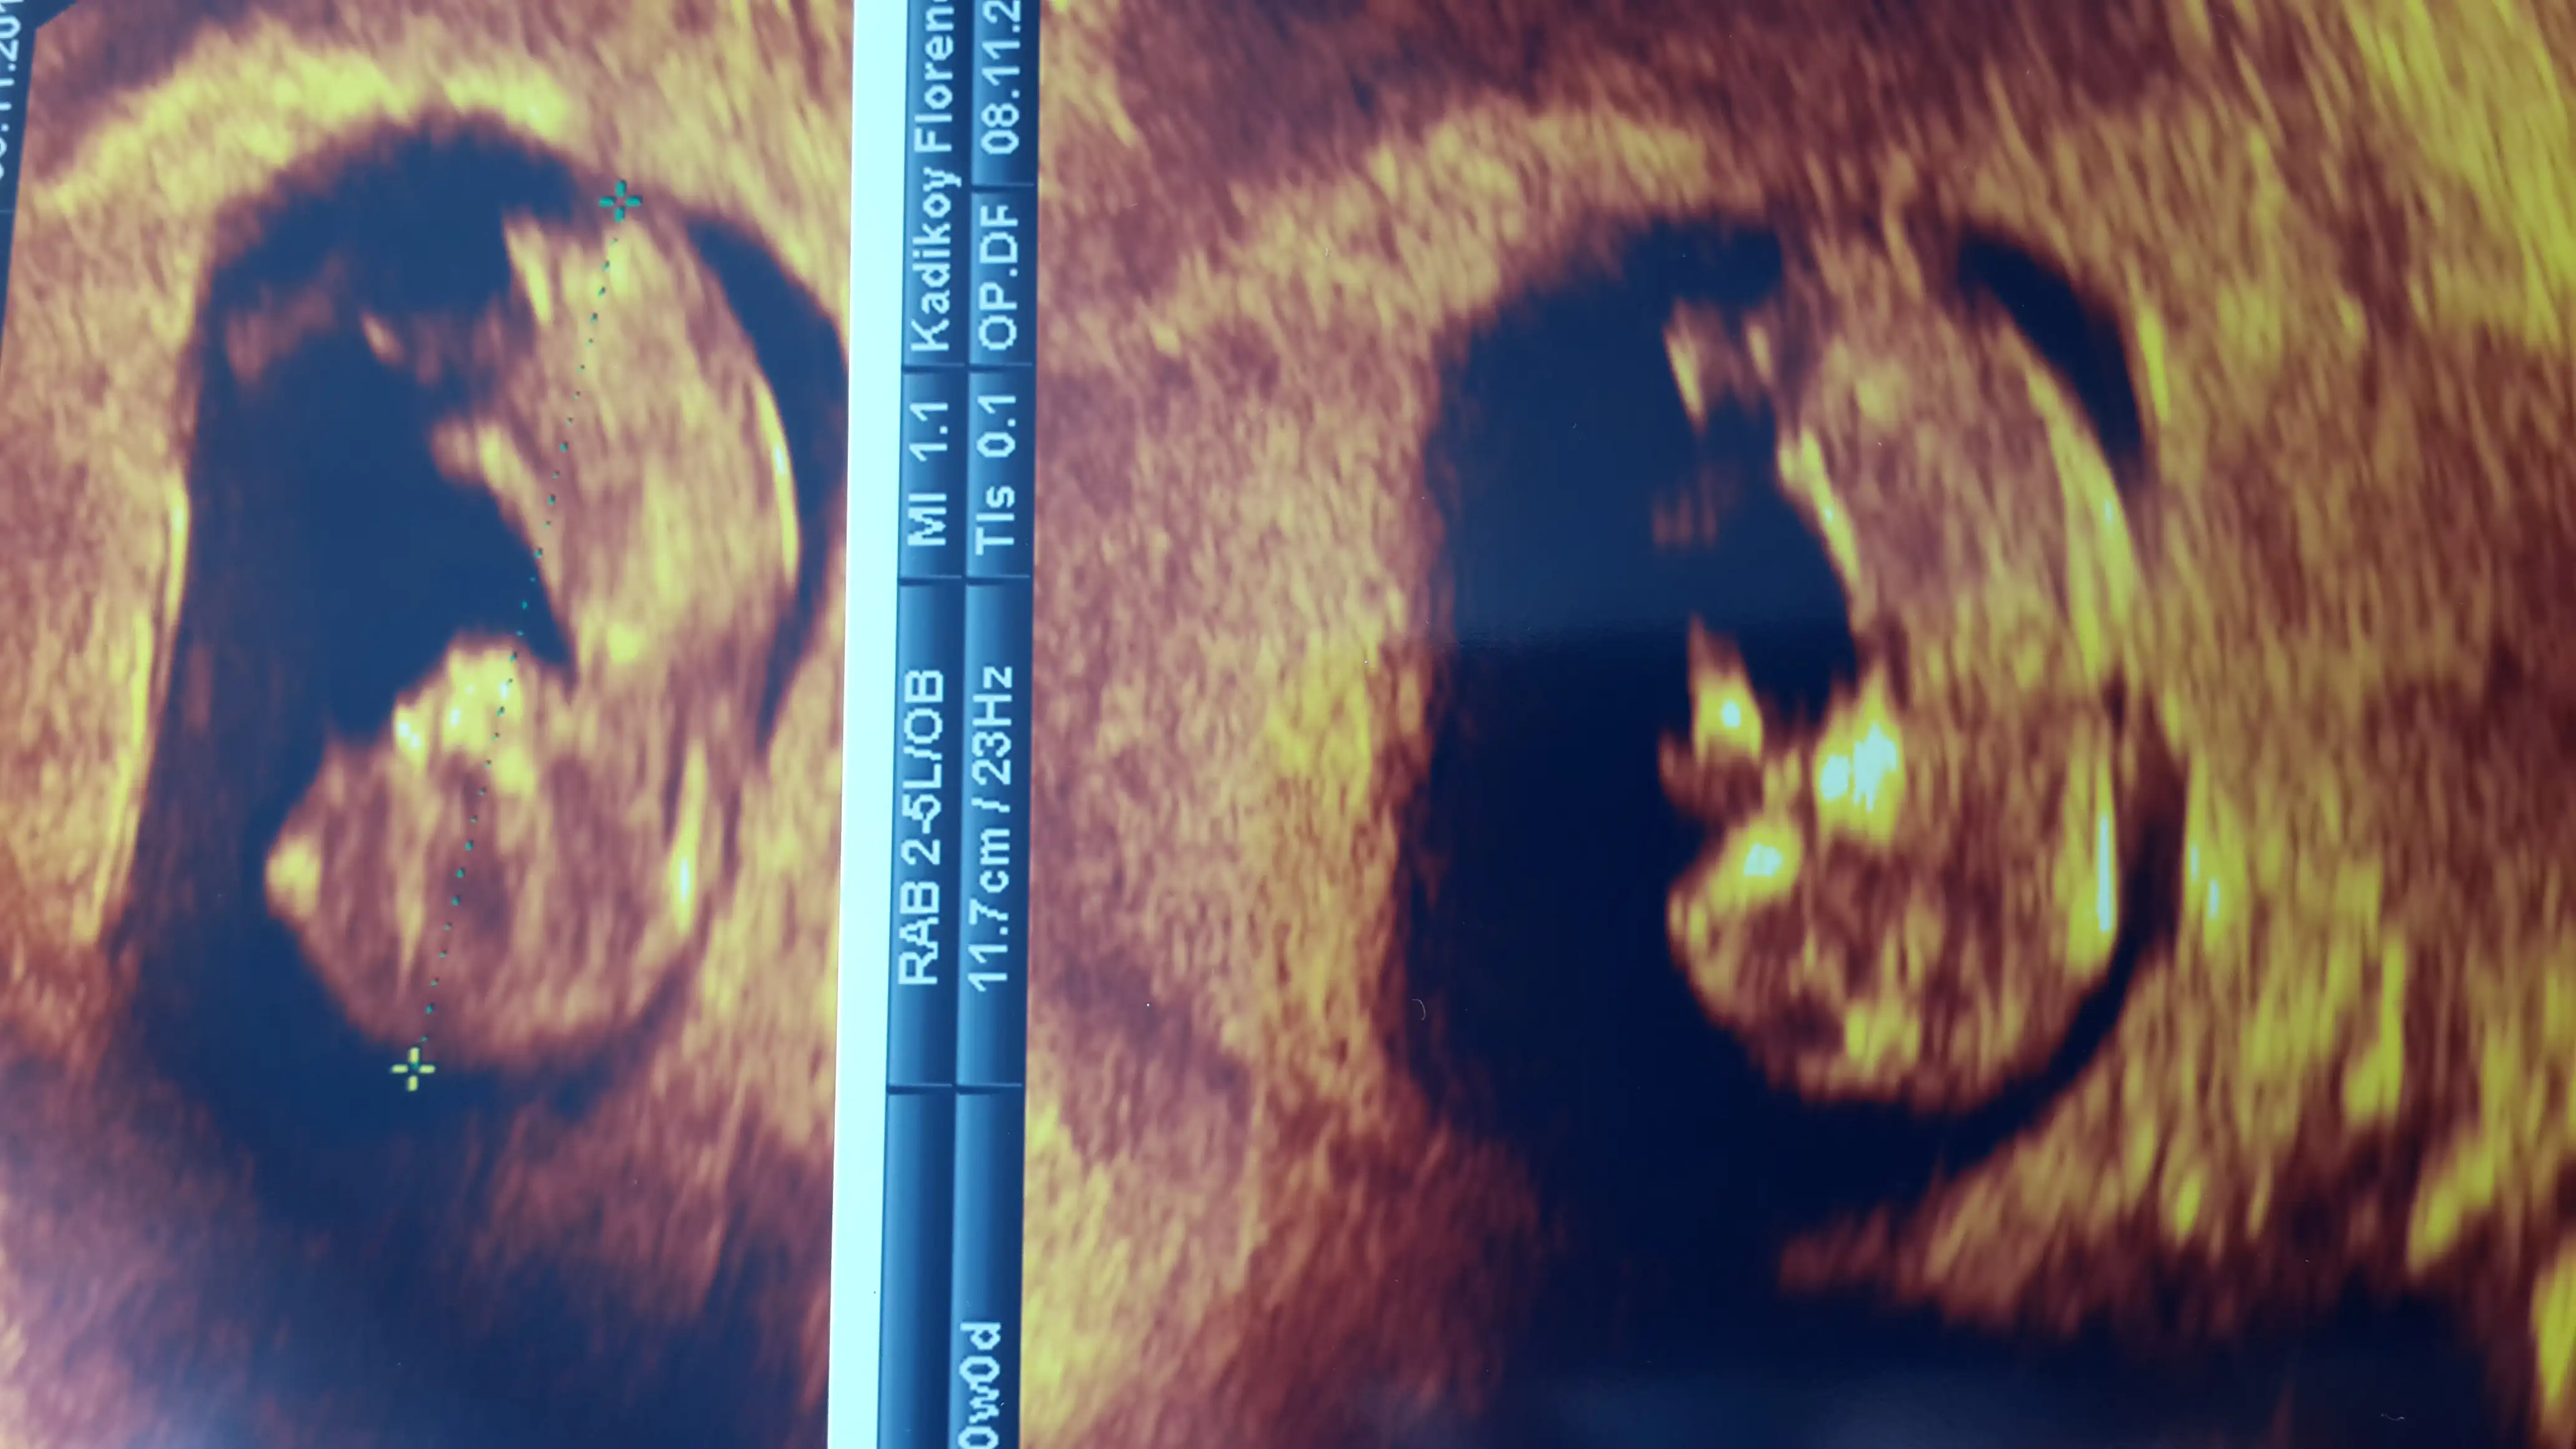

Sirti donuk ama uccizgi goruyorum kiz galibaArkadaşlar 16 haftalık fotografimizi yüklüyorum.doktorumuz emin olmamakla beraber kız olduğunu düşünüyorum dedi.cok uğraşmasına rağmen bacaklarını açmadı bebeğimizsanırım doktorumuz kemik yapısına göre yaptı ve erkek belirtisi göremiyorum dedi.bir sonraki kontrolümüz 2 hafta sonra, beklemek de cok zor..Eki Görüntüle 1296870 sizlerden yorum yapabilecek varsa cook sevinirim

burası sırtı cnm böbrekleri bile seçiliyor maşallahArkadaşlar 16 haftalık fotografimizi yüklüyorum.doktorumuz emin olmamakla beraber kız olduğunu düşünüyorum dedi.cok uğraşmasına rağmen bacaklarını açmadı bebeğimizsanırım doktorumuz kemik yapısına göre yaptı ve erkek belirtisi göremiyorum dedi.bir sonraki kontrolümüz 2 hafta sonra, beklemek de cok zor..Eki Görüntüle 1296870 sizlerden yorum yapabilecek varsa cook sevinirim